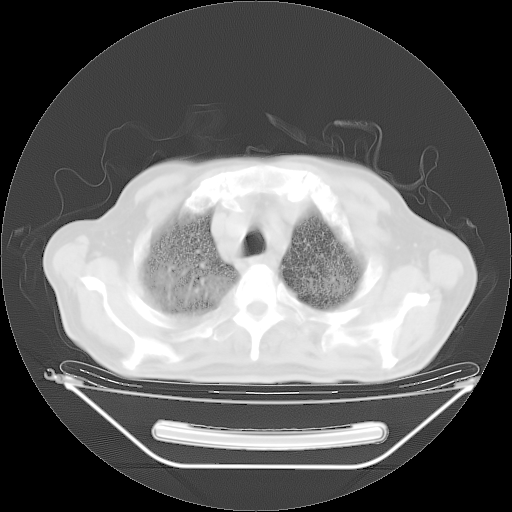

今天复查肺部CT,发现双肺广泛磨玻璃样改变。所以我把3月19日和5月9日相隔50天的肺部CT上传。请大家会诊。

2009年3月19日肺部CT片。

2009年3月19日肺部CT

大致读了系列胸部CT:纵隔窗无明显异常,肺窗:从4、27至今:主要是双肺中下野外带可见毛玻璃样改变,目前处于急性肺泡炎阶段,至于原因考虑1、结替组织或胶原血管性疾病所致?2、恶性疾病如恶组在肺部所致的表现或细支气管肺泡癌?3、药物或其它原因如肺蛋白沉着症所致肺泡炎目前不太可能?总之,明天就去请我院的呼吸科、感染科、血液科和临免专家会诊哈。